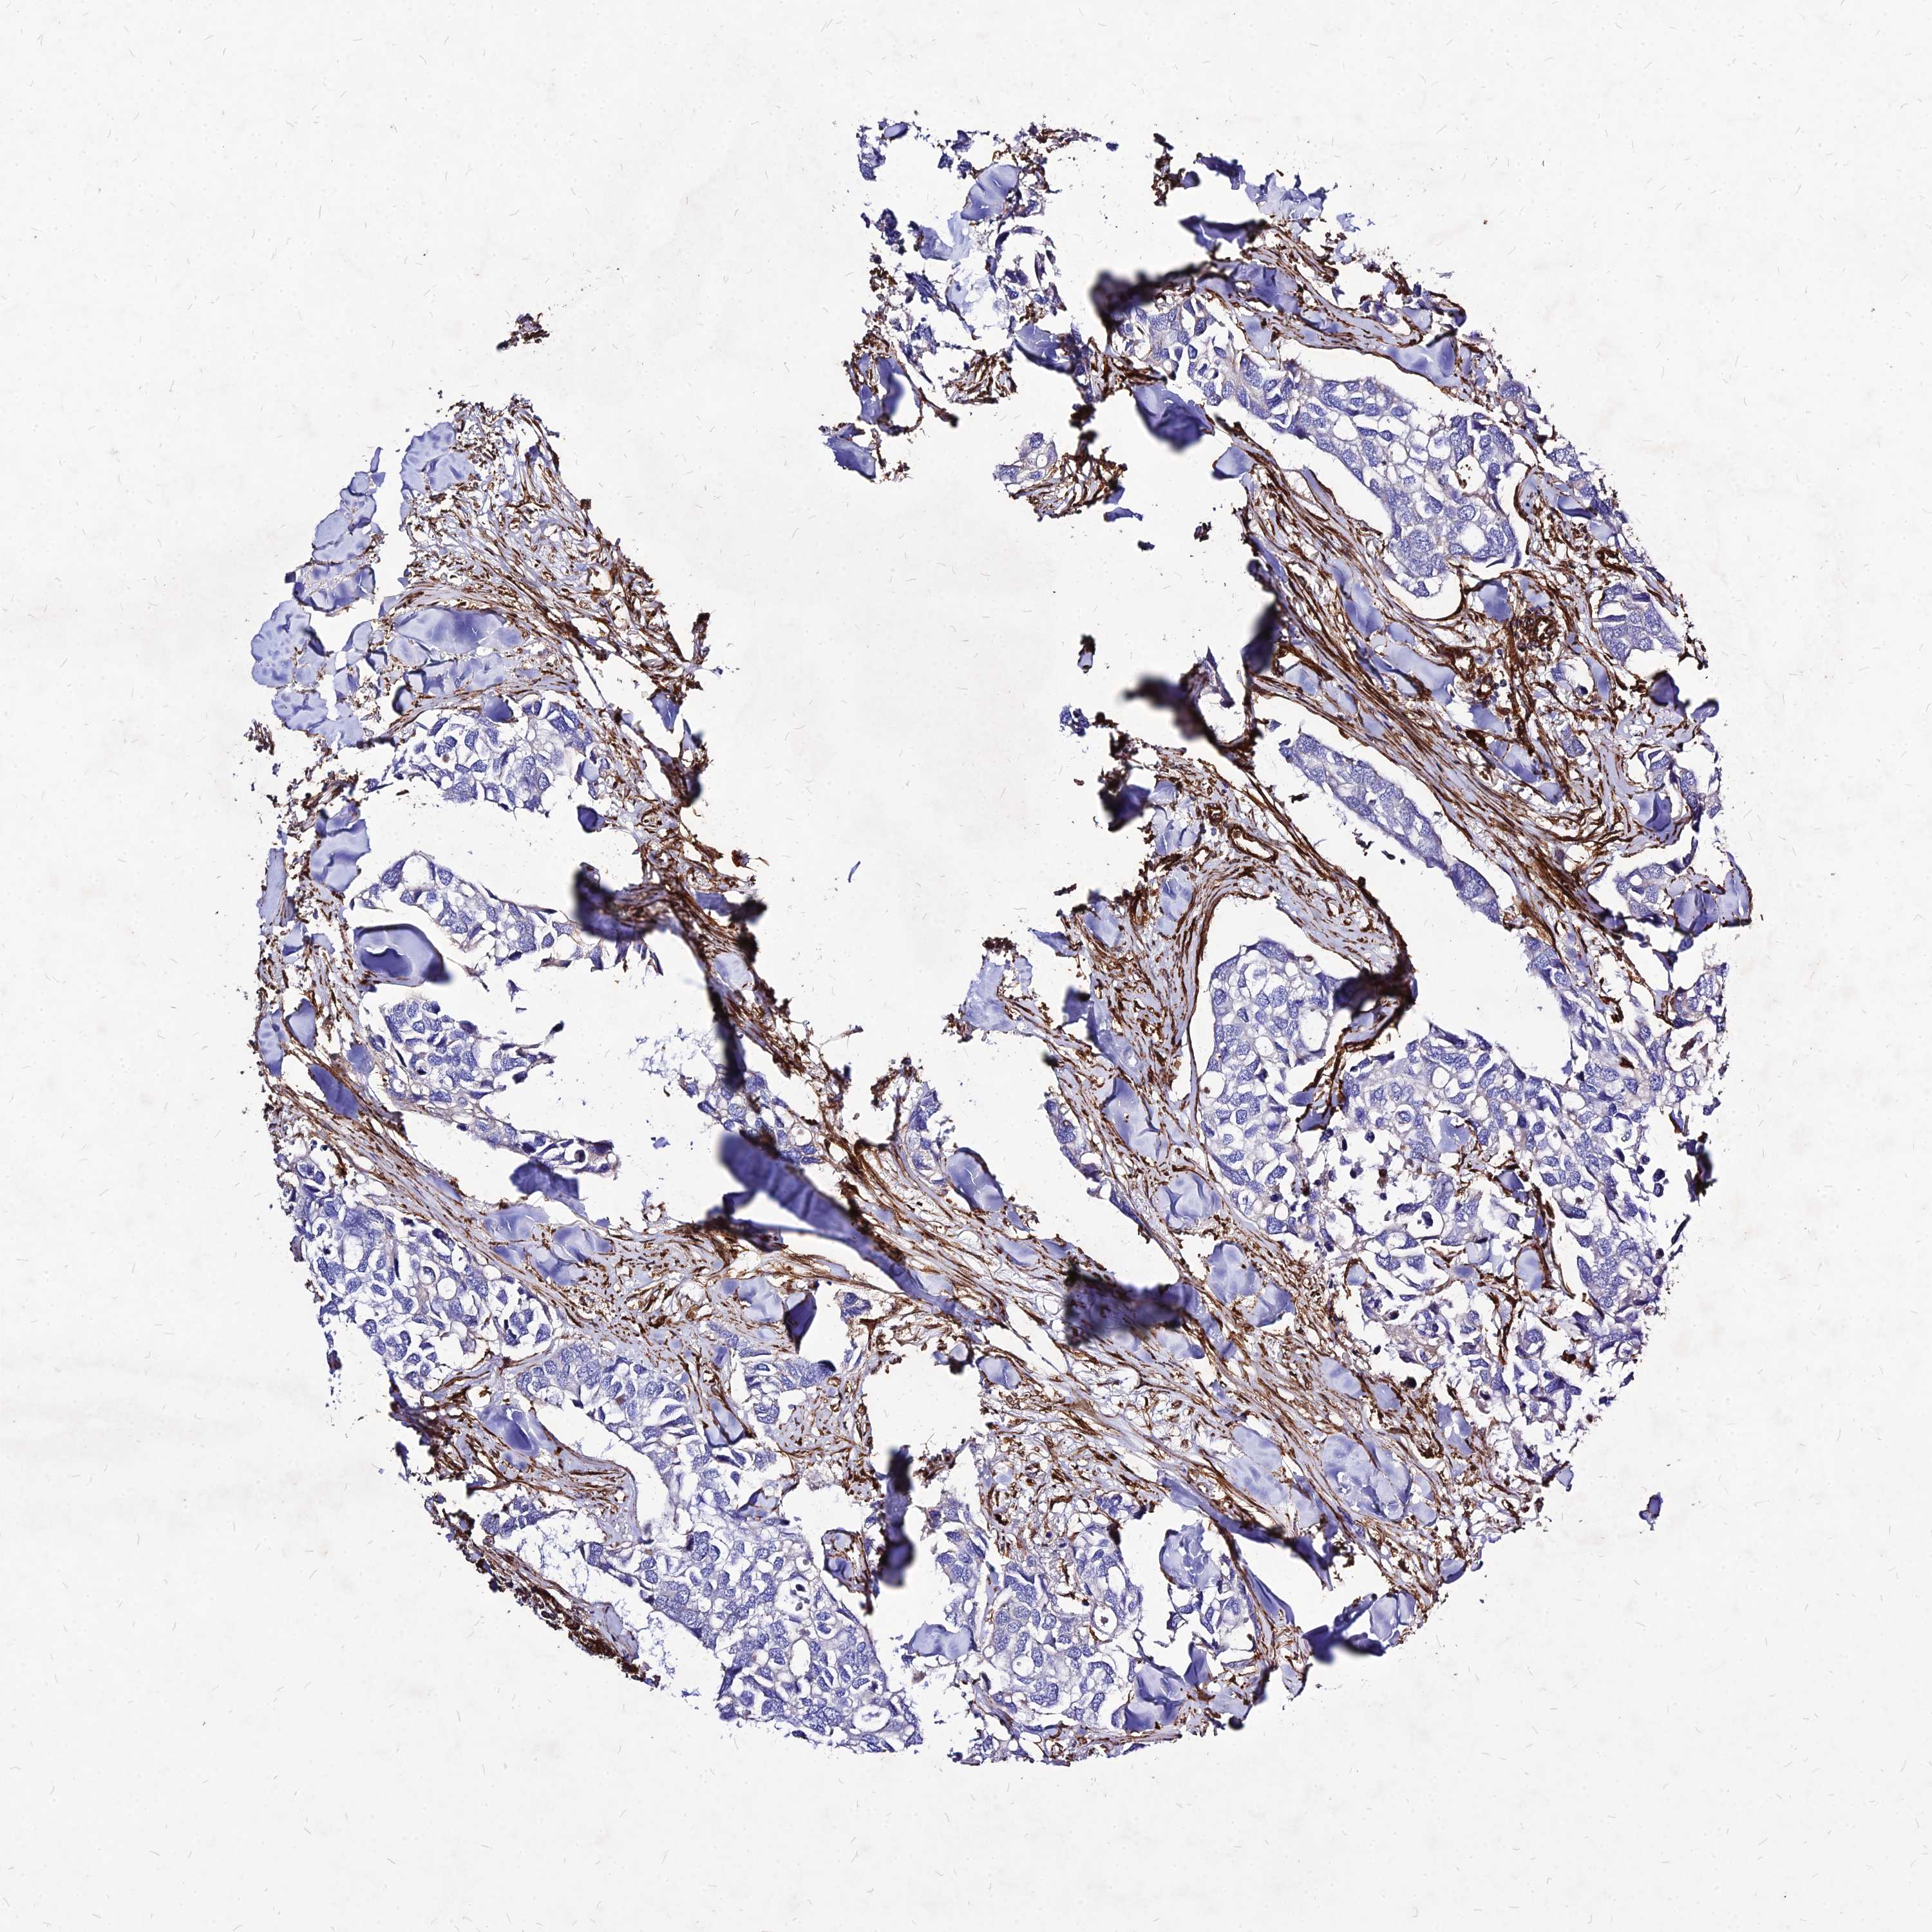

CANCER BREAST CANCER Show tissue menu

BRCA TCGA BRCA VALIDATION PROTEIN EXPRESSION